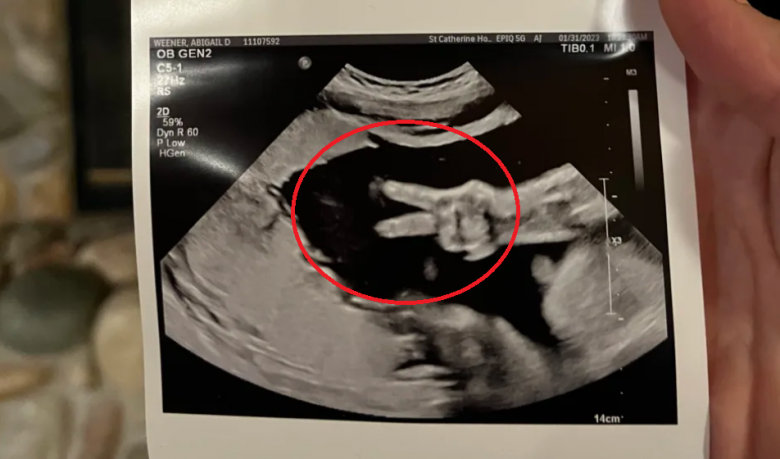

Cặp đôi Kyle và Abby Weener ở Hammond, nước Mỹ đã có một kỷ niệm đầy bất ngờ và ngọt ngào khi đi siêu âm thai nhi. Người cha đã có cuộc trò chuyện với tờ Yahoo Life để chia sẻ khoảnh khắc thú vị mà mình đã trải qua tại Bệnh viện St. Catherine ở Đông Chicago.

Người cha cho biết: "Khi bác sĩ chỉ tay vào màn hình và nói rằng: 'Đứa trẻ đang giơ hai ngón tay kìa'. Và tất cả chúng tôi đều nhìn thấy khoảnh khắc thú vị ấy và bật cười vui vẻ. Dường như con gái chúng tôi cảm nhận được sự xuất hiện của cha mẹ nên đã giơ hai ngón tay biểu hiện sự chào hỏi, vui mừng".

Em bé giơ hai ngón tay giống như gửi lời chào đến bố mẹ.

Bác sĩ siêu âm nói rằng họ chưa bao giờ nhìn thấy khoảnh khắc đáng yêu như thế này trước đây. Chắc hẳn bé gái này sẽ là một đứa trẻ tinh nghịch, hoạt bát và vui vẻ. Anh Kyle cho biết mình và vợ Abby đã có hai người con là bé trai Ezra, 5 tuổi và con gái Eliza, 1 tuổi. Cặp đôi dự định sẽ đặt tên cho em bé sắp chào đời là Eleanor. "Chúng tôi rất mong được gặp con gái trong tháng 4 này", người cha chia sẻ.